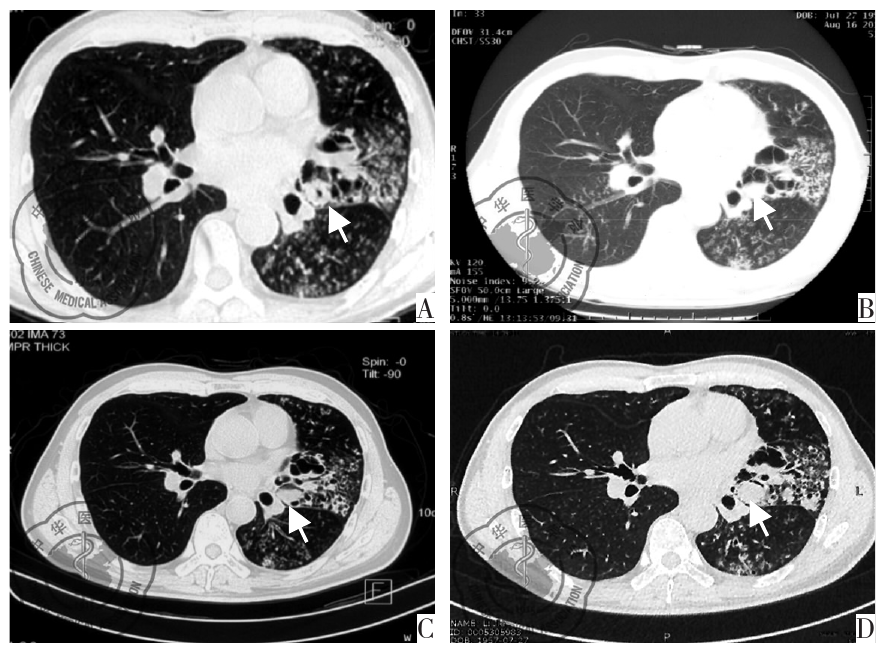

图2 患者2018年4月17日(A),2019年8月16日(B),2020年3月2日(C),2021年4月1日(D)胸部CT变化,可见左舌叶空腔内软组织密度填充影(箭头所示)逐渐增大